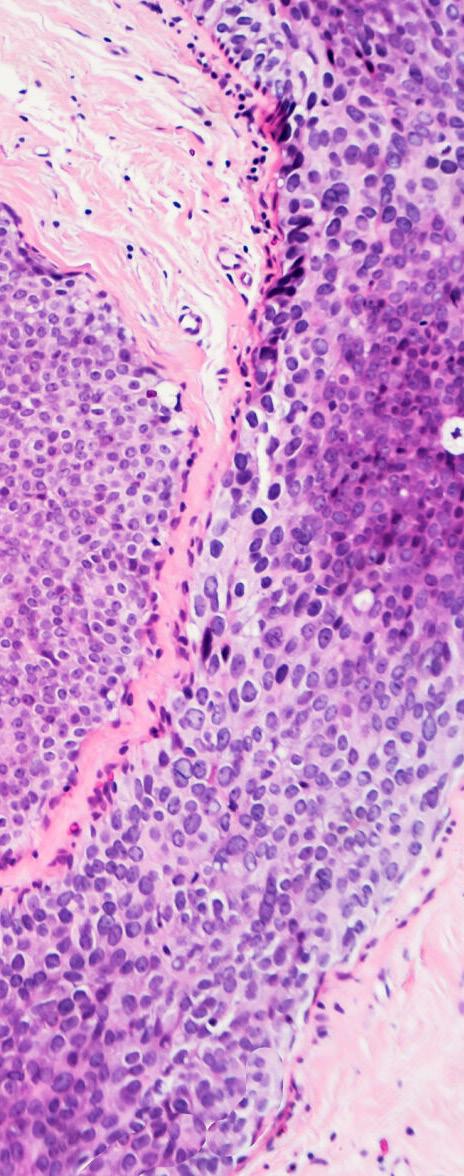

Relación de la vitamina D y la reparación del ADN en mujeres con cáncer de seno

En Puerto Rico, al igual que en otros países del mundo, se estima que una de cada ocho mujeres será diagnosticada con cáncer de seno a lo largo de su vida. En Estados Unidos, este representa la segunda causa de muerte relacionada a cáncer en mujeres. Sin embargo, el cáncer de seno

representa la causa principal de muerte por cáncer en mujeres puertorriqueñas.

Usualmente, el cáncer de seno afecta a mujeres mayores de 50 años. No obstante, la enfermedad también puede afectar a mujeres más jóvenes.

El cáncer de seno es una enfermedad en la cual las células del seno se dividen sin control. Es una enfermedad compleja y su desarrollo se puede atribuir a varios factores incluyendo genéticos —relacionados al ADN—, epigenéticos, y ambientales.

Debido a la complejidad de esta enfermedad, el cáncer de seno se ha subdividido en lo que se conoce como subtipos moleculares. La clasificación de estos subtipos se basa en ciertas características del tumor y, dependiendo del subtipo, existen alternativas de tratamiento específicas que pueden mejorar la sobrevida de las pacientes.

El Ponce Research Institute (PRI) de la Ponce Health Sciences University se ha especializado, entre otros, en estudiar la reparación del ADN en mujeres puertorriqueñas bajo la

supervisión del Dr. Jaime Matta. La reparación del ADN es la capacidad que tienen las células del cuerpo para prevenir daño directo al material genético —ADN— y a su vez, evitar mutaciones que podrían eventualmente contribuir al desarrollo de cáncer.

Estudios previos en el PRI han señalado que el tener una reparación genética reducida es un factor de riesgo para el desarrollo de cáncer de seno. Razón por la que se estudió la relación entre la vitamina D y la reparación del ADN en mujeres puertorriqueñas con cáncer de seno.